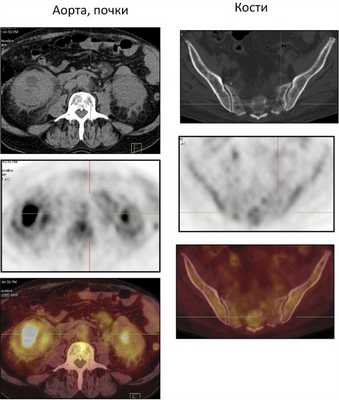

Рис. 4. ПЭТ/КТ брюшной полости (почки, аорта, кости таза).

Из анамнеза: перенес холецистэктомию в 2011 г., наблюдался в поликлинике по поводу ишемической болезни сердца, атеросклероза аорты и коронарных артерий, гипертонической болезни I стадии; аллергологический анамнез без особенностей, наследственность не отягощена. Больным себя считает с марта 2014 г., когда по поводу нарастающей слабости, периодического повышения температуры тела и артериального давления (АД) до 170/100 мм рт.ст. обратился в поликлинику по месту жительства. При компьютерной томографии (КТ) органов брюшной полости и забрюшинного пространства и органов малого таза с внутривенным контрастным усилением омнипаком 350—100 мл выявлены признаки каликопиелоэктазии обеих почек (более выражено справа), инфильтративные изменения стенок лоханок в верхней трети обоих мочеточников, выраженные инфильтративные изменения паранефральной клетчатки с обеих сторон, лимфаденопатия брыжейки тонкой кишки с перифокальной инфильтрацией клетчатки. В легких патологических изменений не выявлено. С диагнозом: болезнь Ормонда наблюдался у уролога и получал терапию 20—30 мг преднизолона. При лабораторном обследовании выявлялась умеренная воспалительная активность: л. (11—15)·10 9 /л; СОЭ 36—68 мм/ч, α 1 -глобулины 7,4% (норма 2,3—6,4%), С-реактивный белок 15,1—35,6 г/л; незначительная гипергаммаглобулинемия до 20% (норма 11—18%) в отсутствие в крови ревматоидного фактора (РФ) и онкомаркеров (ПСА, СА-19—9 и РЭА). Заболевание протекало волнообразно, но в январе 2015 г. у больного появился отек век и стал нарастать экзофтальм. Больной направлен на консультацию в НИИР. При осмотре: кожа век пигментирована. На веках ксантелазмы различной величины (см. рис. 1). Лагофтальм 3 мм справа и 4 мм слева. Ограничение подвижности глазных яблок во всех отведениях. Конъюнктива век, переходных и полулунных складок отечны. Складка бульбарной конъюнктивы вдоль всего края нижнего века с двух сторон. Слезный ручей невысокий, ток слезы замедлен. Пальпебральные доли слезных желез увеличены в размерах, отечны, сосуды резко расширены. Другие органы без особенностей. При ультразвуковом исследовании (УЗИ) щитовидной железы выявлены диффузные изменения по типу хронического тиреоидита. Уровни гормонов щитовидной железы в пределах нормы, антитела к тиреоглобулину и тиреоидной пероксидазе не выявлялись. По данным магнитно-резонансной томографии головного мозга и глазниц, картина выраженного двустороннего экзофтальма, который может соответствовать периневральной форме идиопатического псевдотумора глазничной клетчатки с воспалительно-отечными (реактивными?) изменениями слезных желез и мышц глазниц. Исследование с использованием ядерного магнитного резонанса головы выявило единичные мелкие очаги в белом веществе головного мозга, вероятно, сосудистого генеза. КТ брюшной полости и забрюшинного пространства. В полости перикарда определяется незначительное количество жидкости, шириной в области переднего листка до 0,7 см. Печень умеренно увеличена в размерах, структура и плотность ее не изменены. Отмечаются выраженное уплотнение и тяжистость паранефральной клетчатки, обе почечные ножки на этом фоне дифференцируются нечетко. На уровне L II —L IV аорта муфтообразно окружена мягкоткаными структурами, толщина которых достигает 1,2 см. Подобного характера изменения определяются и в области нисходящей аорты на уровне T IX —T X . Кпереди от тел нижнегрудных позвонков визуализируется стелящийся инфильтрат толщиной до 1,3 см. В брыжейке тонкой кишки множество увеличенных до 1,8×1,6 см ЛУ без четких контуров. Компьютерно-томографическая картина не противоречит болезни Ормонда. При сравнении с данными от 2014 г. имеется выраженная отрицательная динамика в виде прогрессирования склеротических изменений и явлений гидронефроза с обеих сторон (больше справа), со значительным замедлением экскреторной функции почек. Для исключения лимфопролиферативного процесса целесообразно дополнительное обследование. При УЗИ глаза и глазницы выявлены признаки выраженного отека век и экзофтальма, значительное увеличение размеров изображения, так называемого стандартного плоскостного ультразвукового среза слезных желез «по глубине и ширине» (OD 2,27×1,52 см; OS 2,23×1,03 см). С обеих сторон имеется неравномерное значительное увеличение толщины прямых глазодвигательных мышц, больше с правой стороны (OD 0,52×0,56 cм; OS 0,48×0,53 см). С правой и левой стороны, между зрительным нервом и прямыми глазодвигательными мышцами, имеются области разряжения, которые особенно хорошо видны с внутренней стороны. При иммунологическом исследовании: высокочувствительный (вч) СРБ 105 мг/л (норма 65 г/л), значительное повышение уровня вчСРБ 181,5 мг/л (норма 5 г/л). Выполнено иммуногистохимическое исследование (ИГХИ) биоптата с использованием антител CD138, IgG, IgG4, panCK, CD20, CD3, CD68 (PGM-1). Полиморфно-клеточный инфильтрат представлен множеством гистиоцитов, СD68 + с примесью лимфоцитов, большая часть которых является Т-лимфоцитами, CD3 + . В-лимфоциты в виде отдельно расположенных небольших групп клеток CD20 + . Плазматические клетки CD138 + в большом количестве, большая часть которых является позитивными по IgG плазмоцитами. При реакции с IgG4 позитивны лишь единичные клетки, составляющие менее 10% позитивных клеток по IgG (что можно объяснить, вероятно, предшествующей терапией стероидами). Заключение: учитывая данные анамнеза и морфологическую картину, следует предполагать заболевание, ассоциированное с IgG4. Исследование, выполненное на проточном цитофлуориметре, выявило увеличение процентного и абсолютного количества Т-клеток (CD3 + 89,3%; 2,2·10 9 /л), Т-цитотоксических клеток (CD3 + CD8 + 44,8%; 1,0·10 9 /л), снижение процентного и абсолютного количества В-клеток (CD19 + CD3 – 0,3%; 0,008·10 9 /л). С учетом неэффективности ранее проводимой терапии глюкокортикостероидами (ГКС) больному начата комбинированная терапия ритуксимабом и эндоксаном, которая является оптимальным лечением при IgG4-CCЗ [29—31]. Внутривенно капельно с премедикацией 500 мг солюмедрола введены 1000 мг ритуксимаба и 1000 мг эндоксана 1 раз в 2 нед (2 вливания на курс) с последующим введением эндоксана 1 раз в 14 дней (4 на курс) и поддерживающей терапии метилпреднизолоном 4 мг. При оценке эффективности терапии через 4 мес объективно сохранялся выраженный экзофтальм, периодически отмечался подъем температуры до фебрильной. При лабораторном исследовании отмечено снижение показателей воспалительной активности (Hb 136 г/л, л. 11,5·10 9 /л, тр. 433·10 9 /л, СОЭ 50 мм/ч по Вестегрену (норма до 20 мм/ч), вчСРБ 15,2 мг/л, снижение уровня IgG4 до 2,1 г/л. Наблюдалось полное истощение B-клеток CD19 + в крови. При мультиспиральной КТ (МСКТ) глазниц после внутривенного введения 100 мл визипака в отсроченную фазу в ретробульбарной клетчатке определяется мягкотканое образование с неровными контурами, полностью выполняющее полости глазниц, гомогенной структуры, размерами справа 3,3×4,3×3,5 см, слева 3,3×3,7×3,6 см. Мышцы глаз, слезные железы на этом фоне нечетко дифференцируются. Зрительные нервы окружены мягкоткаными разрастаниями, истончены. Определяется двусторонний экзофтальм. Костно-деструктивных изменений нет. Выполнена МСКТ органов брюшной полости после контрастирования желудочно-кишечного тракта до и после введения везипака. Заключение: проявление ретроперитонеального фиброза. Умеренная двусторонняя пиелоэктазия. Умеренная гепатомегалия. Состояние после холецистэктомии. Незначительный перикардит. Множественные увеличенные ЛУ брыжейки тонкой кишки. При сравнении с данными КТ от 2015 г. без динамики. С учетом прогрессирования клинических проявлений псевдотумора глазниц (см. рис. 2, рис. 3), отсутствия положительной динамики при МСКТ глазниц и органов брюшной полости на фоне терапии, некоторых необычных клинических (периодические подъемы температуры до фебрильной, наличие множественных ксантелазм век) и морфологических (наличие большого количества гистиоцитов и недостаточного количество плазмоцитов, секретирующих IgG4, при ИГХИ для постановки диагноза IgG4-ССЗ) проявлений решено провести дополнительное обследование больного с пересмотром биоптатов для исключения системного варианта гистиоцитоза. Проведена позитронно-эмиссионная томография (ПЭТ) для исключения генерализованного гистиоцитоза. Заключение: данных о наличии агрессивного лимфопролиферативного заболевания, а также другого неопластического процесса не получено. Псевдотумор глазниц, генерализованный фиброз медиастинальный, внутрибрюшной, внутритазовый и забрюшиной клетчатки с минимальным воспалительным компонентом. Изменения по типу «волосатой почки» и «облицованной аорты». Внутрибрюшная лимфоаденопатия, вероятнее всего, реактивного генеза. Двусторонний пневмофиброз, застойные (?) изменения в базальных отделах легких. Двусторонний гидронефроз. Гепатомегалия. Генерализованная мелкоячеистая перестройка костей скелета (остеопороз?). Накопление препарата в скелете, вероятнее всего, за счет раздражения костного мозга (см. рис. 4). При К.Т. нижних конечностей и костей черепа выявлены множественные остеосклеротические изменения в дистальных отделах бедренных и большеберцовых костей (рис. 5) и плоских костях черепа (рис. 6). Сцинтиграфия костей: выявлены множественные склеротические перестройки костного мозга. Симметричная патологическое избыточное накопление радиофармпрепарата (РФП) в костях лицевого скелета, эпифизах, метафизах и метадиафизах трубчатых костей наиболее выраженное в бедренных, большеберцовых и костях стоп. Повышенное накопление в чашечно-лоханочной системе правой почки. Однофотонная эмиссионная КТ/КТ черепа и коленных суставов: очаги патологического избыточного накопления РФП соответствуют склеротической перестройке костного мозга. Пересмотр гистологических препаратов с ИГХИ: среди полиморфно-клеточного инфильтрата большое количество гистиоцитов, пенистых клеток, скопления плазматических клеток. Гистиоциты СD68 + , S100 – , IgG4 + , единичные плазматические клетки. Субстрат поражения может принадлежать гистиоцитозу, учитывая локализацию следует предполагать БЭЧ (см. рис. 7). Методом полимеразной цепной реакции в реальном времени с анализом кривых плавления (Rotor Gene 6000) выполнено молекулярное исследование биоптатов. В 599—601-м кодонах 15-го экзона гена BRAF мутация не обнаружена. На рис. 8 представлена частота повторяющихся клинико-радиологических находок у больных БЭЧ, согласно данным литературы и в нашем случае заболевания. Таким образом, больному диагностирован генерализованный гистиоцитоз: БЭЧ с конституциональными нарушениями (лихорадка, патологическая утомляемость, снижение массы тела), поражением кожи и области глазниц (ксантелазмы век, экзофтальм, псевдотумор глазниц, дакриоаденит), костей (остеосклеротические поражения бедренных, малоберцовых и плоских костей черепа), поражение сердечно-сосудистой системы (выпотной перикардит, поражение грудной и брюшной аорты по типу «облицованной аорты»), ретроперитонеальных проявлений (гидронефроз, пиелоэктазия за счет инфильтрации околопочечной ткани по типу «волосатой почки») c отрицательной мутацией BRAFV600E.